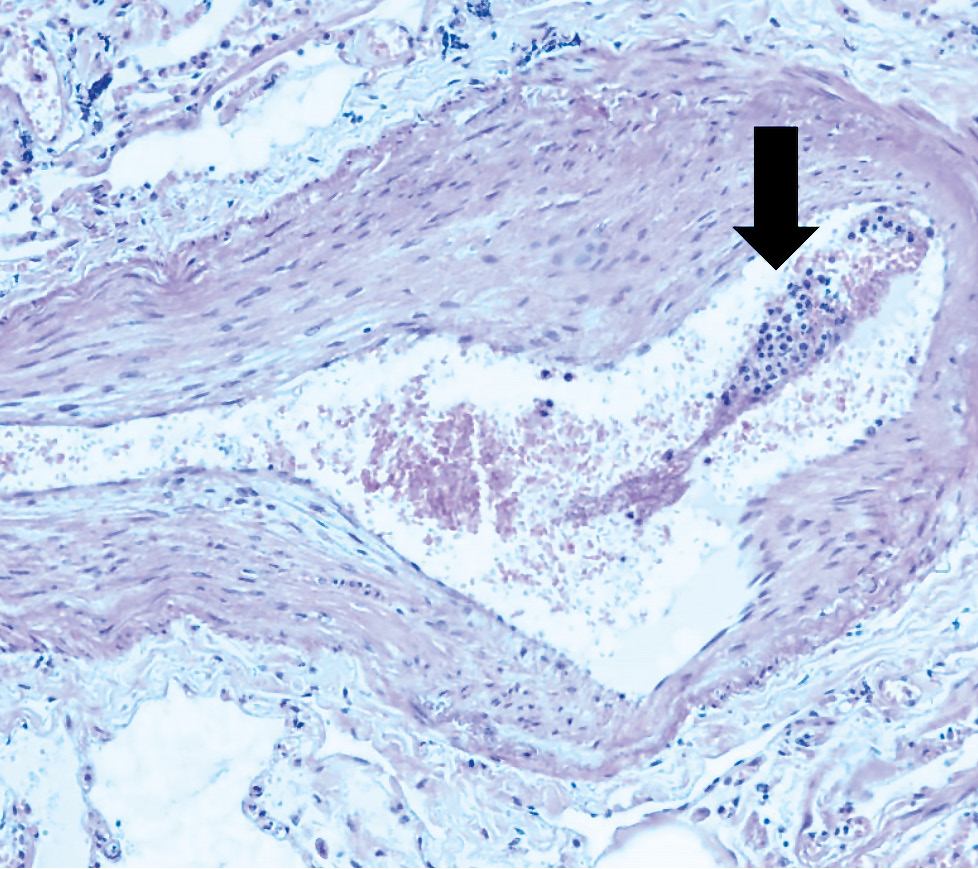

Однако по результатам аутопсии основным заболеванием установлена лимфома Ходжкина. Обнаружено значительное увеличение лимфоузлов средостения и опухолевый конгломерат размерами 14×7×6,5 см в области расположения бифуркационных и прикорневых лимфоузлов. Диффузный рост серовато-белесоватой плотноэластичной ткани наблюдался в жировой клетчатке средостения, в зоне бифуркации трахеи и корней лёгких с распространением на сосудистый пучок основания сердца и прилежащий перикард (рис. 6). На перикарде и эпикарде отмечен налёт фибрина, со стороны эпикарда обращали на себя внимание множественные узловые разрастания опухолевой ткани (рис. 7). Также опухолевая ткань в виде узлов с тромботическими наложениями выступала в полость ПП. Выявлены тромбы единичных мелких ветвей лёгочных артерий. В миокарде ПЖ и МЖП обнаружен рост опухолевой ткани, замещающей миокард, с прорастанием эндокарда, корня аорты, истока лёгочной артерии (рис. 8). В миокарде ЛЖ от эпикарда и интрамурально — также участки разрастания опухолевой ткани. В зонах опухолевого роста толщина стенки ЛЖ составила 1,8–1,9 см, правого — до 1,5 см. Гистологическое исследование тканей позволило выявить диффузную полиморфноклеточную инфильтрацию и клетки Ходжкина и Рида–Березовского–Штернберга (рис. 9), также опухолевые клетки определены в составе тромбов (рис. 10). В плевральных полостях обнаружено значительное количество жидкости (слева — 1100 мл, справа — 1500 мл). Следует отметить, что в коронарных артериях присутствовал распространённый (более 50% площади) атеросклеротический процесс, однако бляшки были стабильными, в стадии обызвествления, со стенозами до 50%.

Рис. 9. Клетка Рида–Березовского–Штернберга (указана стрелкой). Микропрепарат (окраска гемотоксилин-эозином, ×200).

Fig. 9. The Reed–Berezovsky–Sternberg cell (indicated by the arrow). Micropreparation (hemotoxylin-eosin staining, ×200).

Рис. 10. Опухолевые клетки в составе тромбоэмболов в лёгочных артериях (указаны стрелкой). Микропрепарат (окраска гемотоксилин-эозином, ×100).

Fig. 10. Tumor cells in the thromboemboli in the pulmonary arteries (indicated by the arrow). Micropreparation (hemotoxylin-eosin staining, ×100).